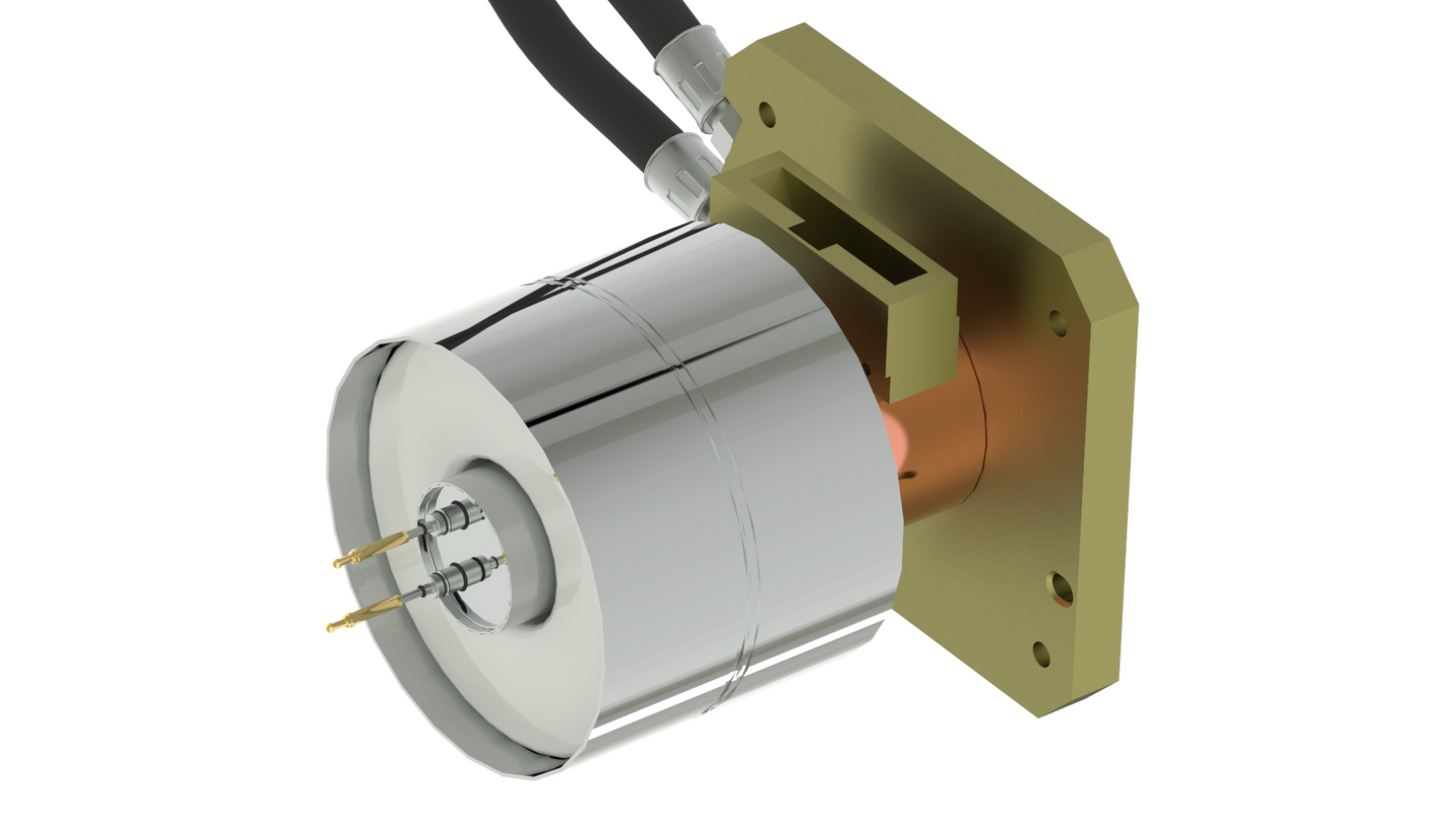

Whether portable in the Intensive Care Unit, or mobile in the ambulance as a Mobile Stroke Unit, SOMATOM On.site is designed to bring critical care imaging to your patients. With the first-of-its-kind telescopic gantry design, integrated positioning accessories, and proven SOMATOM technologies, you can achieve fast and reliable CT head imaging.

The first-of-its-kind telescopic gantry allows for easier patient positioning, minimizes motion artifacts, and provides radiation safety for staff and neighboring patients.

Proven SOMATOM technologies such as Stellar detector, iMAR, and ADMIRE® provide high image quality, enabling faster clinical decisions for critical care patients.

Technical Details

Scanner type

Head CT scanner

Detectors

2.4 cm Stellar detector